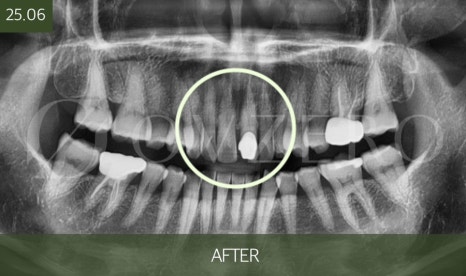

What happens if you delay root canal treatment?

If the timing for root canal treatment is missed,

inflammation around the tooth root can worsen,

leading to a situation where the tooth can no longer be saved.

In that case,

a treatment that could have ended with

root canal treatment → a crown

may change to

extraction → implant or bridge.

Tooth treatment is structured in a way that,

as time passes,

the scope gets wider and the burden increases as well.

So the point where "I can still endure it" often turns out to be

the best time to treat it.